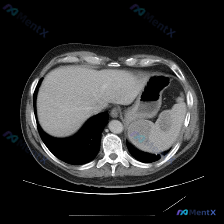

今天看到一个挺有意思的影像分析场景:拿到一张上腹部CT横断面(软组织窗),问题直接指向“脾脏病变”,但仔细看完影像描述,我觉得这里可能藏着一个临床思维的小陷阱。先把资料理一理: --- 影像描述核心信息整理 肝脏:轮廓清晰,形态正常,肝实质密度均匀,未见明确局灶性占位,肝内血管走行自然。 脾脏:左上...

整理了一个很有意思的读片资料,先看一下基本情况: 影像资料概况 - 扫描部位:上腹部横断面CT(软组织窗) - 图像质量:清晰,对比度适中,无明显运动伪影 - 显示结构:肝脏、胃、脾脏、腹主动脉、椎体及周围软组织 主要影像描述(按器官整理) - 肝脏:形态轮廓尚平滑,实质密度均匀,未见明显局限性肿块...

今天看到一份很有意思的腹部CT读片案例,整理一下思路和大家分享。 病例背景 用户最初的问题是「识别图中的脾脏病变」,但拿到图像(腹部CT横断面软组织窗)后,先按流程做了系统评估。 --- 影像关键信息整理 先把看到的客观情况列出来: 1. 脾脏:形态大小正常,包膜光滑,密度均匀,未见任何局灶性异常,...

最近看到一个读片资料,预设问题是“图像中是否存在脾脏病变”,先和大家理一下完整的思路。 --- 先列一下拿到的「影像客观事实」 这是一幅上腹部CT软组织窗横断面图像: 1. 肝脏:轮廓平整,实质密度均匀,肝内血管走行清晰,无受压移位; 2. 脾脏:划重点——形态正常、大小正常、实质密度均匀,未见局灶...